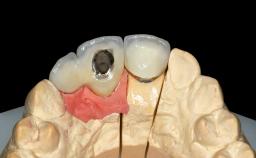

A 45-year-old woman was referred for management of an infection associated with two implant-supported crowns replacing the maxillary central incisors. Two tissue-level implants had been placed and restored with cemented single metal-ceramic crowns in those sites 4 years previously. The patient presented with a draining sinus (i.e. a pathological duct from an abscess cavity to a surface) 3 mm from the midfacial peri-implant mucosal margin of the maxillary right implant crown. She was in good general health, did not smoke, showed a good oral hygiene status, and had no history of periodontal disease. The implants were well positioned. While the patient was very satisfied with the appearance of her crowns, she had noted that the peri-implant soft tissue had receded since their insertion and was concerned about the possibility of further recession.

| Retention | Cemented, with prosthesis margin < 3mm submucosal Cemented, with prosthesis margin < 3mm submucosal |